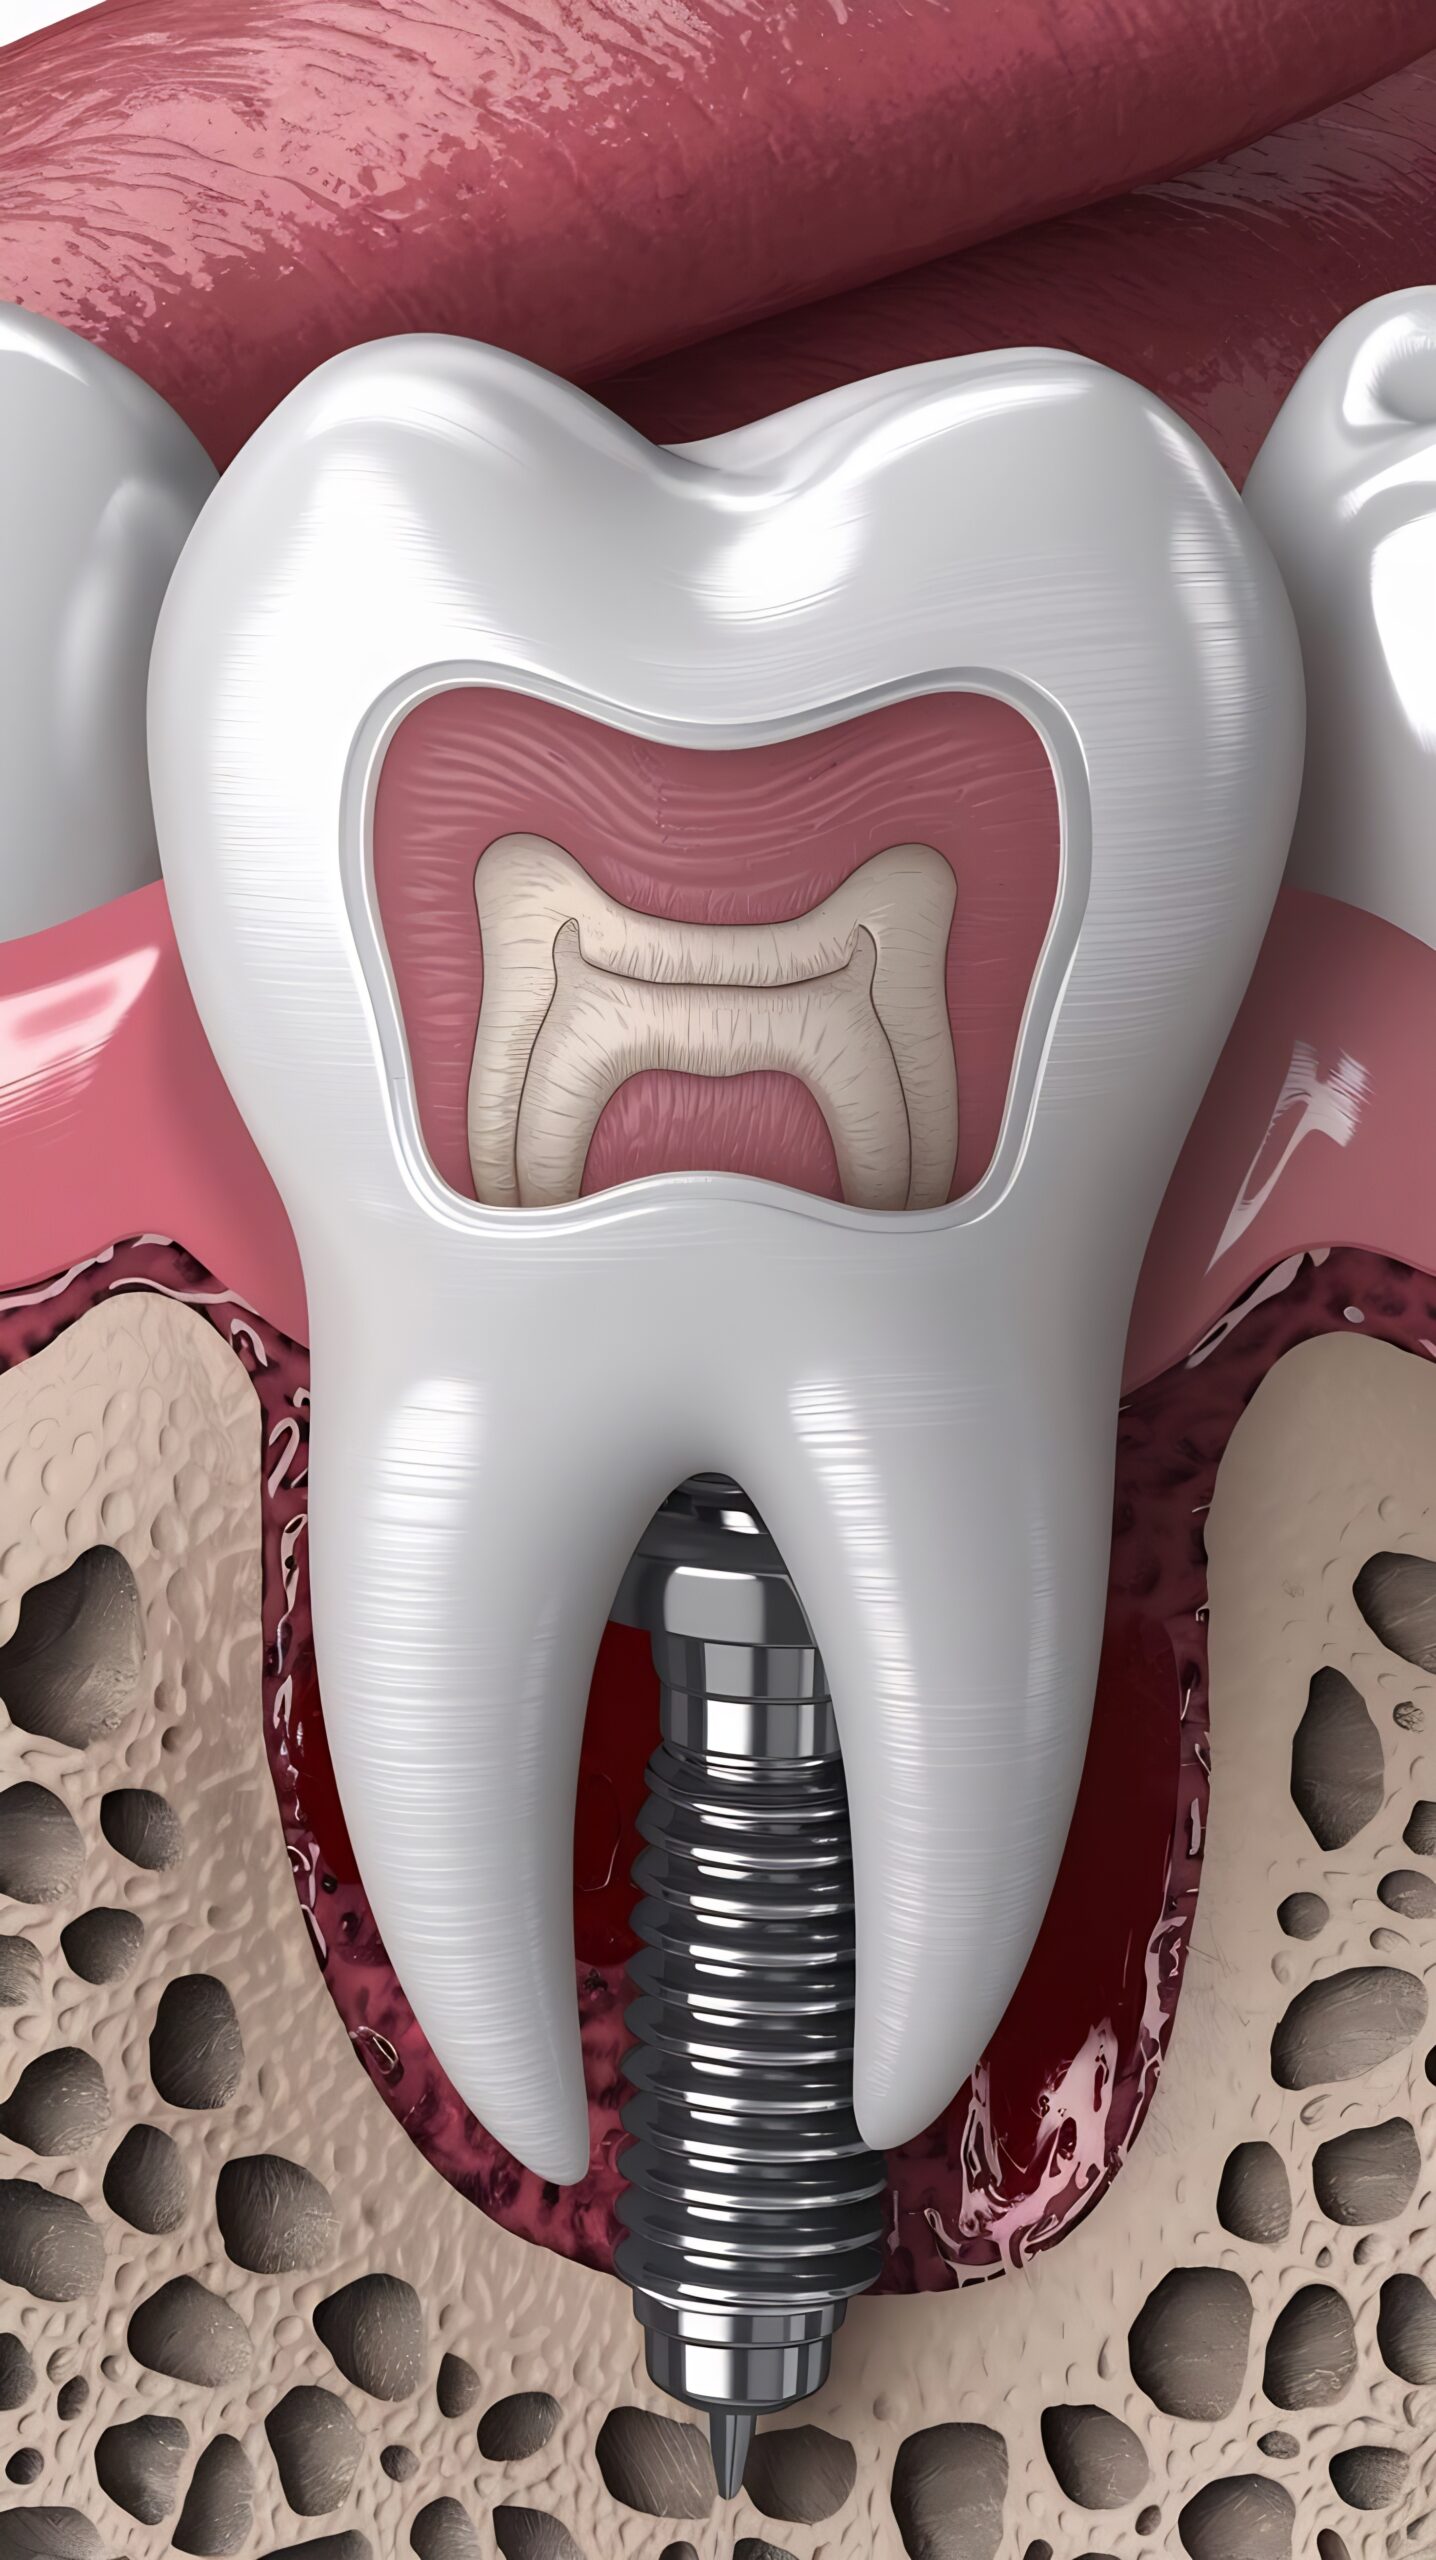

Dental implants are titanium posts that act as artificial tooth roots. They are placed securely into the jawbone to support a crown, bridge, or denture. Because they integrate with the bone, implants provide unmatched stability, durability, and comfort. Whether you’re missing one tooth or several, implants offer a long-lasting and highly aesthetic solution.

At Ivory Dental, The dental implant process is simple, precise, and designed for your comfort. It begins with a thorough consultation and digital planning to assess your needs. The implant is then gently placed into the jawbone, where it naturally bonds over a short healing period. Once healed, a custom-made crown or restoration is attached, completing your new, strong, and natural-looking smile.

Implant Placement

The implant is placed into the jawbone using precise, minimally invasive techniques.

Healing & Integration

Over a few months, the implant fuses with the bone for strong, stable support.